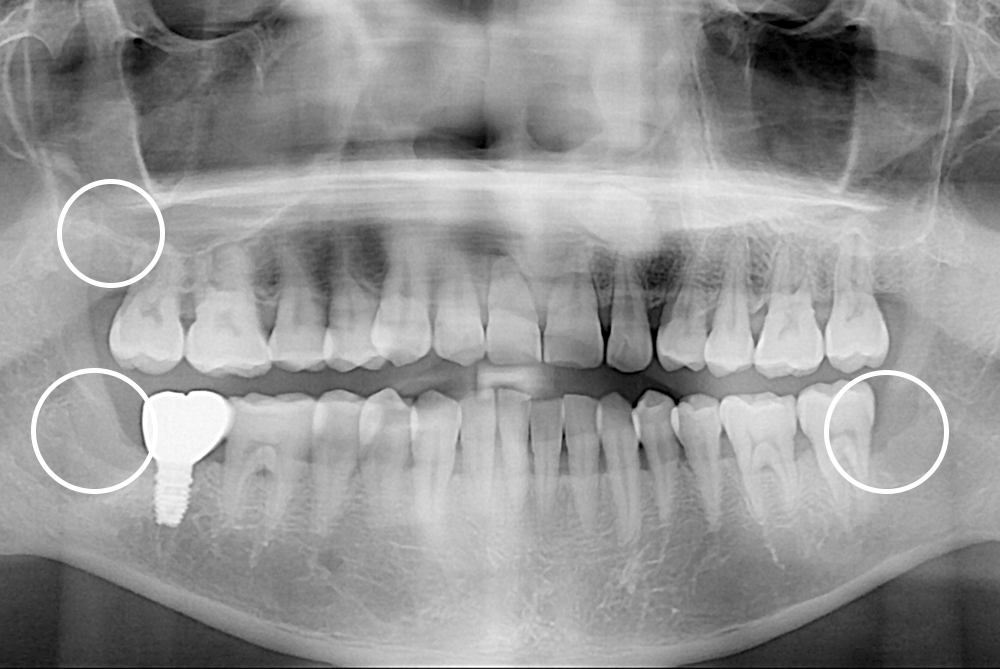

[사랑니] 매복 사랑니 발치

치료전 : 2018-11-30

세종치과는 구강악안면외과학 박사이신 원장님이 발치하는 치과입니다.